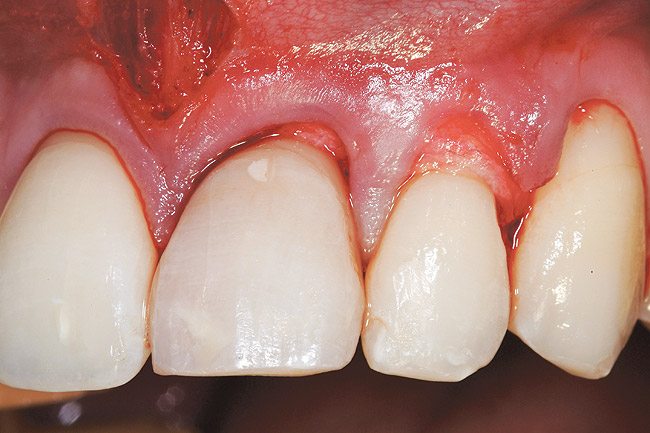

Figure 23  Case Three Atraumatic extraction, left central incisor.

Figure 23

The patient opted for the third option. After administration of an appropriate local anesthetic, a frenectomy was performed using a Nd:Yag laser. This would allow for the loosening of the facial tissues and the coronal repositioning of the pouch at the termination of the procedure. After the frenectomy, the left central incisor was removed by an atraumatic technique preserving the soft tissue emergence profile (Figure 23). Debridement of the extraction socket preceded atraumatic site preparation techniques. A 3.5-mm diameter by 13-mm tapered implant (Prima Connect, Keystone Dental, www.keystonedental.com) was placed to the appropriate depth measurements planned.38,39